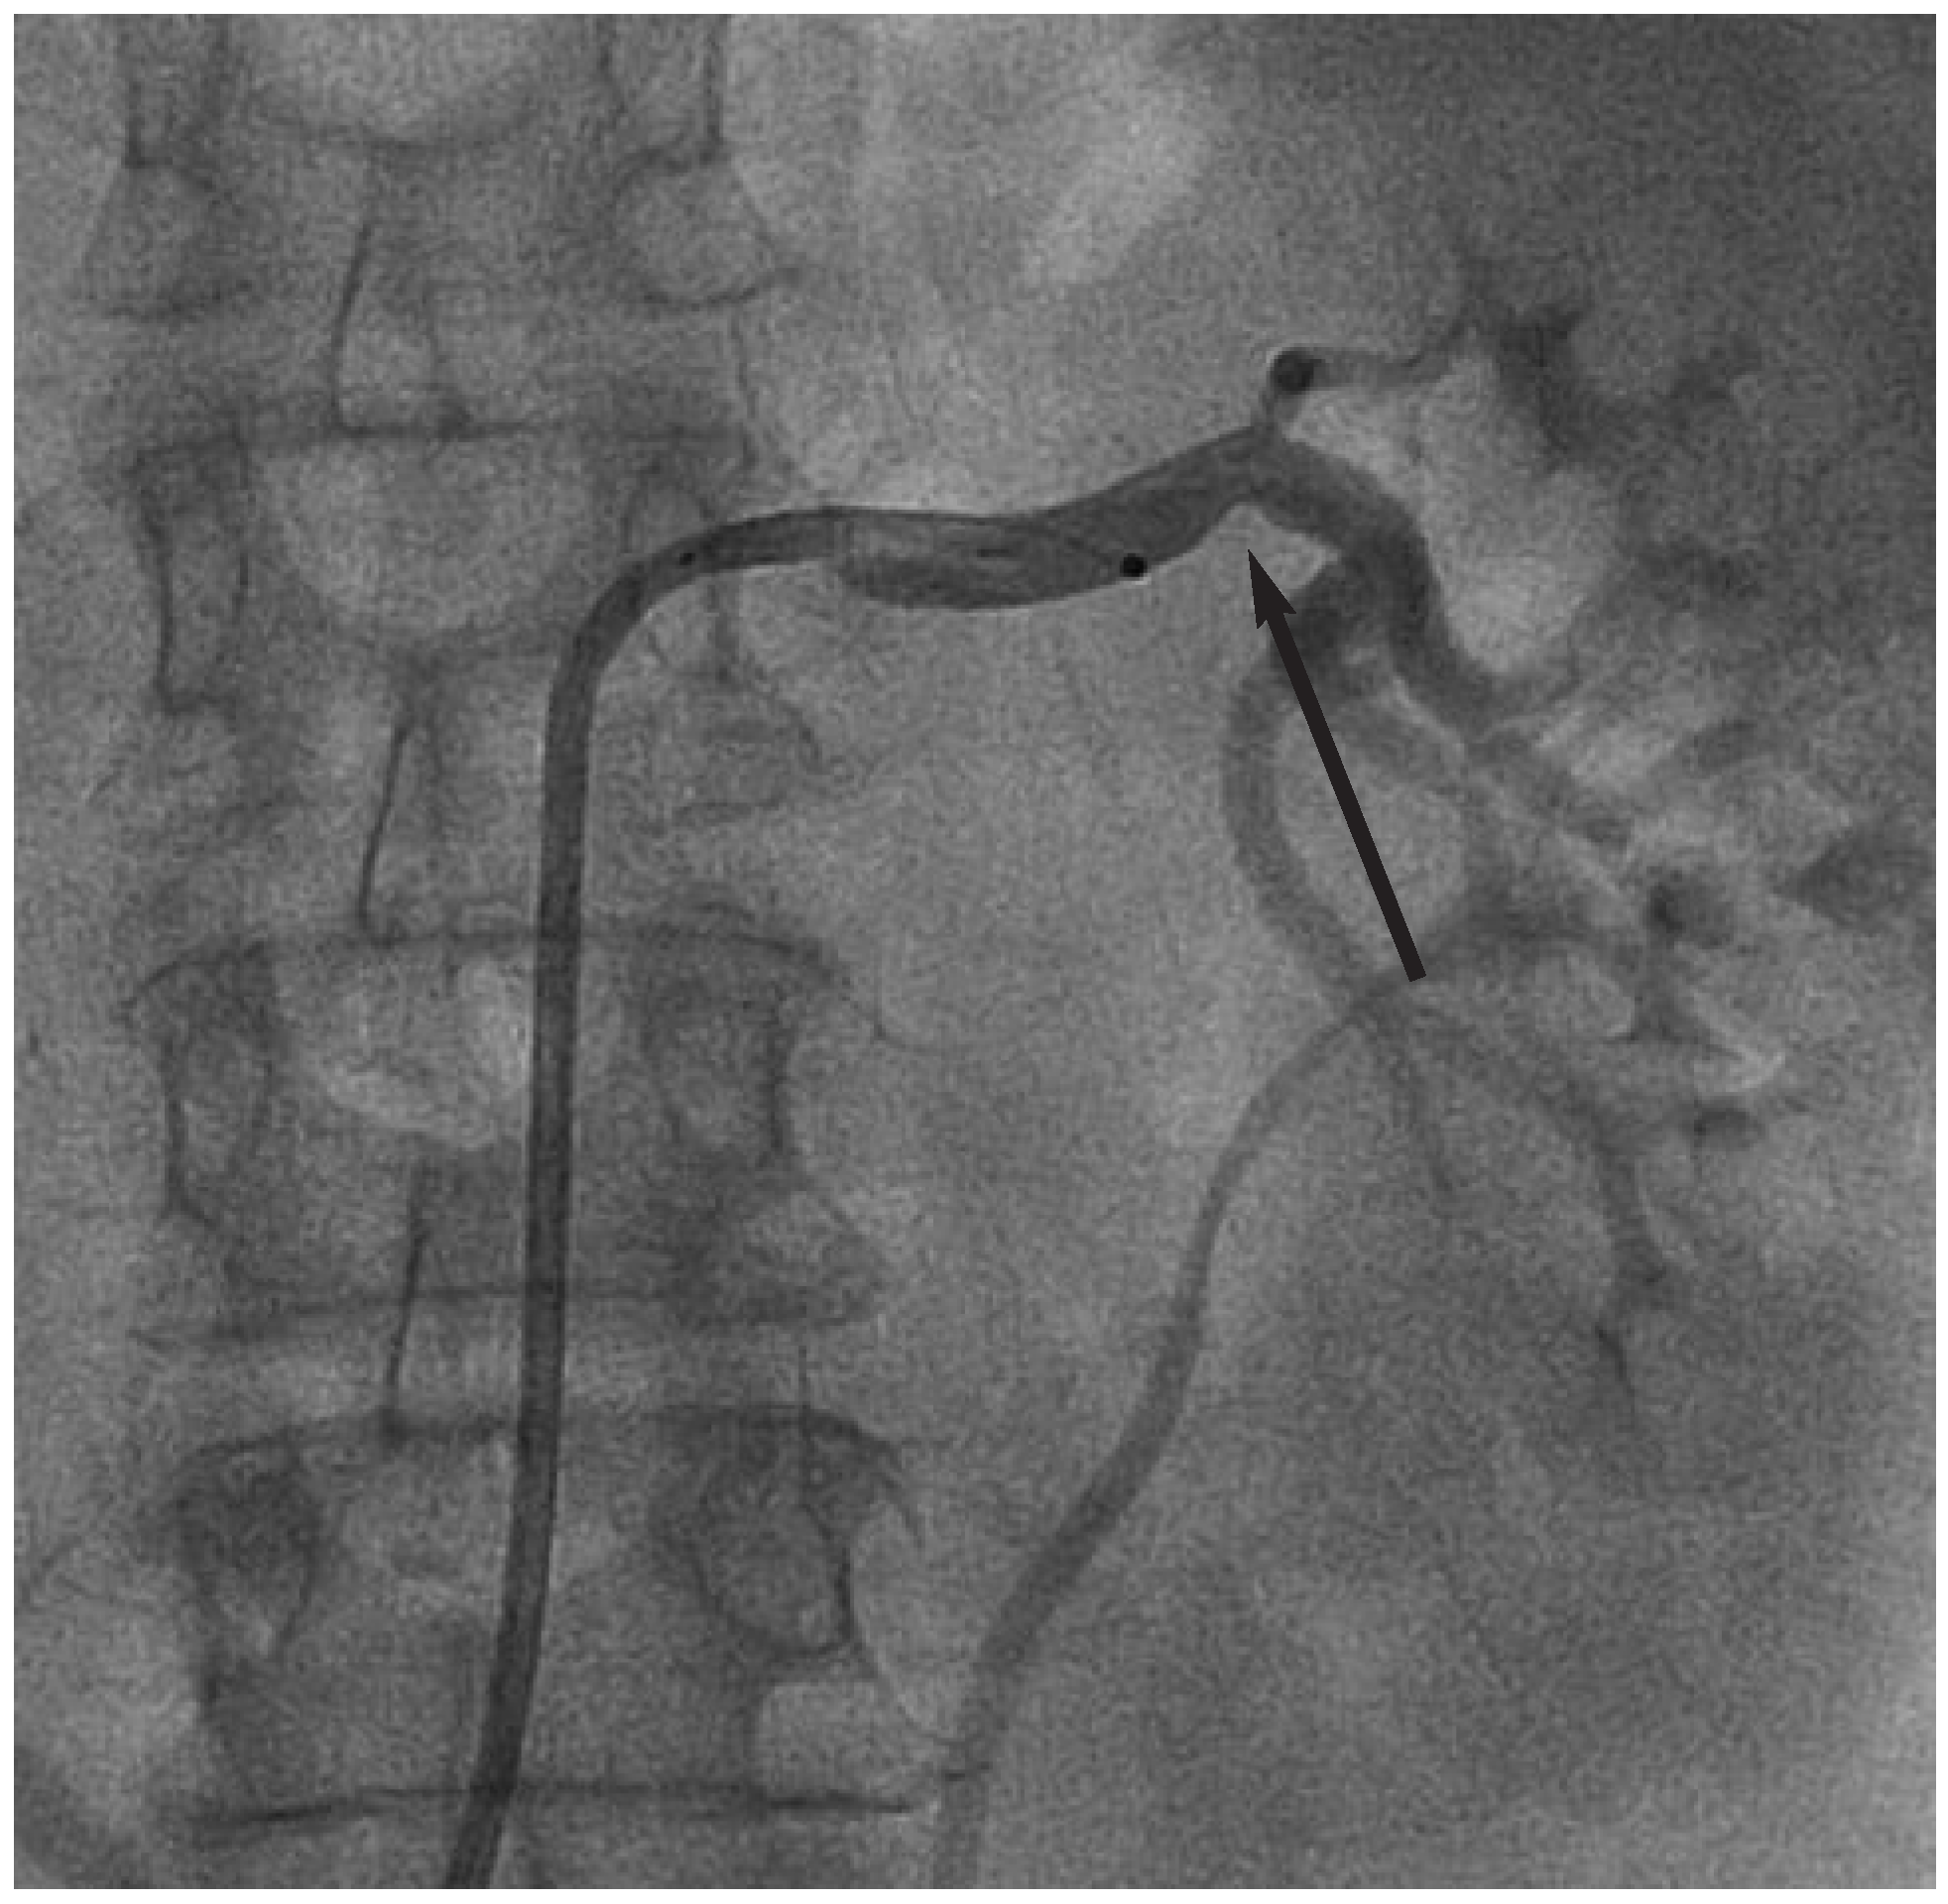

Abbildung 3.

Initiale Darstellung der rechten und linken Nierenarterie zur Überprüfung der Anatomie vor Durchführung der renalen Sympathikusdenervation.

Die Durchführung der renalen Sympathikusdenervation erfolgte im standardmässig eingerichteten Herzkatheterlabor unter monoplaner Durchleuchtung. Die Vorbereitung der Patientin entsprach im Wesentlichen der einer Koronarangiographie. Nach lokaler Anästhesie der vorgesehenen Punktionsstelle erfolgte die Punktion der linken Arteria femoralis. Mittels Seldinger-Technik wurde eine 8-French-Schleuse in das Gefäss eingeführt. Anschliessend erfolgte nochmals die Darstellung der renalen Gefässanatomie (Abb. 3). Es zeigte sich entsprechend dem magnetresonanztomographischen Vorbefund eine geeignete Anatomie beider Nierenarterien. Nun wurde ein 8-French-LIMA-Führungskatheter eingebracht und die linke Nierenarterie intubiert. Über einen Führungsdraht (BMW, Abbott Laboratories, Illinois, USA) wurde in der Folge ein 5-F-Multipurpose-Katheter bis zur Bifurkation der Nierenarterie eingeführt. Nach Rückzug des Führungsdrahtes wurde über den liegenden 5-F-Katheter der Symplicity™-Ablationskatheter in der linken Nierenarterie platziert. Danach wurde der 5-F-Katheter zurückgezogen und ein Kontakt der Spitze des Ablationskatheters mit der Nierenarterienwand hergestellt (Abb. 4).